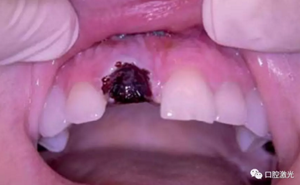

術(shù)后3天